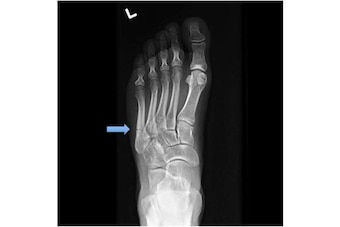

According to Cincinnati Bengals writer Geoff Hobson, Bengals quarterback Andy Dalton will start the season without one of his prime targets, wide receiver Marvin Jones, who is recovering from a foot injury. Jones suffered a broken fifth metatarsal over the weekend, an injury that necessitated surgery.

Fifth metatarsal fractures are not uncommon in football, and an eight-week recovery time is definitely reasonable. The surgical fixation of the fracture will help ensure such a time frame, as fifth metatarsal fractures often do not heal well on their own. Even with surgery, however, nothing is a guarantee.

More than likely, Jones suffered, believe it or not, a so-called "Jones" fracture. A stress fracture—usually occurring in a slightly different location relative to a true Jones fracture, a subtle distinction that is a bit beyond the scope of this article—is also possible.

Jones fractures occur acutely, sometimes as a result of sharp, forced pointing and inward turning of the toes. Stress fractures develop more slowly over time. Both types involve areas of bone without robust blood supplies.

Without strong blood flow, any type of fracture runs the risk of nonunion, a complication describing a fracture that reattaches incompletely or not at all.

During a fifth metatarsal fixation operation, a surgeon—often a foot and ankle specialist—will insert a piece of metal hardware, such as a screw, into the bone. The screw will fix the bone into its proper anatomical position while it heals as best it can. Depending on the unique characteristics of the athlete and injury, the surgeon may also place pieces of bone from elsewhere in the body, called a bone graft, into the area to help stimulate healing.